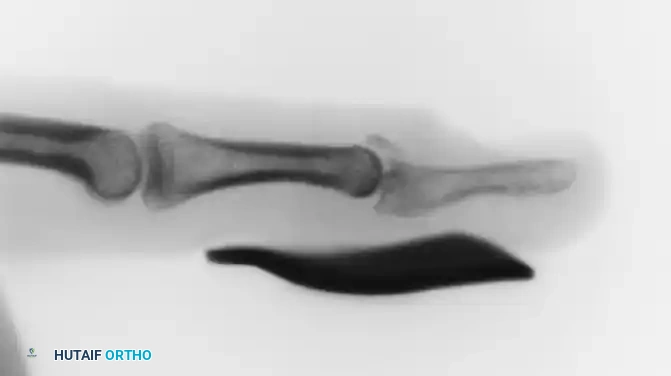

FIGURE 67-64 A and B: Displaced and angulated distal phalangeal fracture associated with a severe nail bed laceration in a 22-year-old patient, demonstrating the classic presentation of a complex open distal phalanx injury.

FIGURE 67-64 C and D: Postoperative radiographic and clinical appearance after precise bone fixation with a K-wire, which provided the necessary stability to permit subsequent realignment and microsurgical repair of the nail bed.